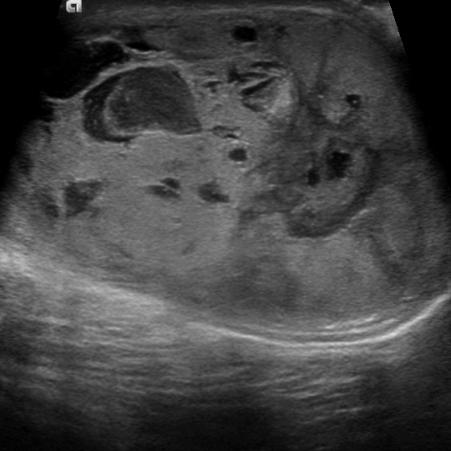

Adult Polycystic Kidney Disease

liver & spleen cysts